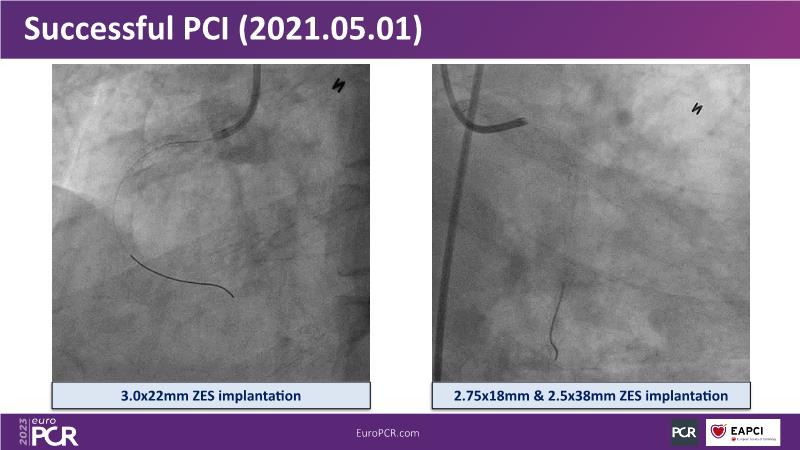

Maximize patient clinical outcomes in complex percutaneous coronary interventions (PCIs) by joining this session. Discover how accurate patient evaluation, advanced imaging/functional modalities, optimized procedures, and the Cre8 EVO device contribute to improved safety and efficacy, and review the challenges associated with DES implantation in complex PCIs.

- To find out how an accurate evaluation of patient profile, imaging/functional modalities, optimised interventional procedure and the proper selection of the device contribute to maximise patient clinical outcomes both in terms of safety and efficacy

- To understand how the Cre8 EVO unique technology and its specific design may contribute to improve the procedural success and clinical outcome of complex PCIs in complex patients